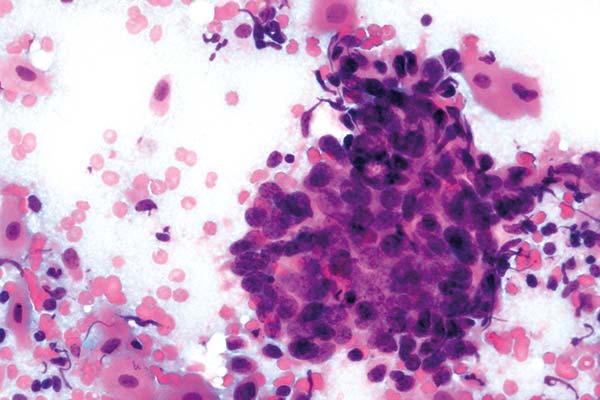

Februar

richtige Antwort:

c. Adenokarzinom des Endometrium (V-e)

- deutlich größere Zellen als bei normalem Endometrium

- Tumordiathese im Hintergrund mit frischen und zerfallenen Ery’s

- Mit zunehmender Entdifferenzierung nimmt die Zell- und Kerngröße zu

- Deutliche Anisonukleose